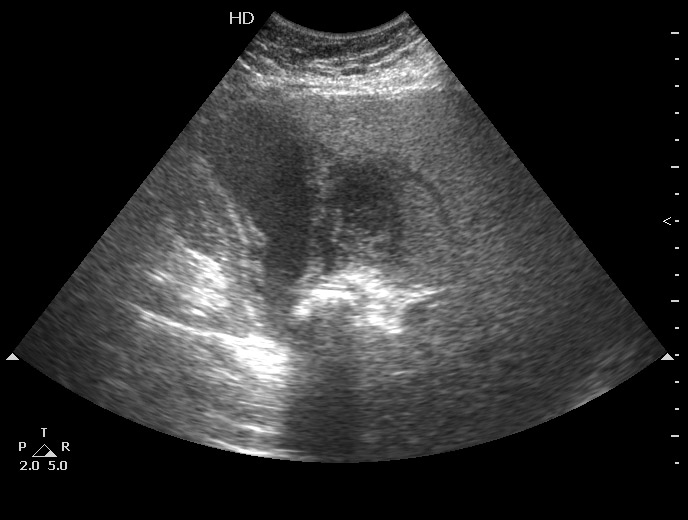

ЖКБ:конкремент в шейке ЖП, стенка пузыря утолщена, неравномерно эхогенна с двойным контуром и на всем протяжении не прослеживается- Эмпиема ЖП - возможно, острый гангренозный холецистит На снимке вокруг ЖП определяется гипоэхогенное образование без четких границ- перфорированный ЖП (гнойный перихолецистит ?) Только почему без температуры???

Вопрос "почему без температуры" волновал и хирургов, пациентку прооперировали через 2,5 недели после поступления, полностью подтвердив Ваше заключение.

Острый калькулезный обструктивный холецистит, эмпиема желчного пузыря, перфорация, околопузырный абсцесс.

антибиотики+особенности ответа организма

Потому что в пузыре дырка и произошла его декомпрессия.